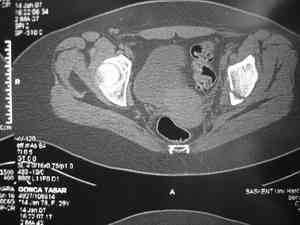

прилагаю пример с такой же давностью травмы, репонировали аппаратом

> в аппарате или одномоментно открыто. Лично я склоняюсь к аппаратному лечению на первом этапе.